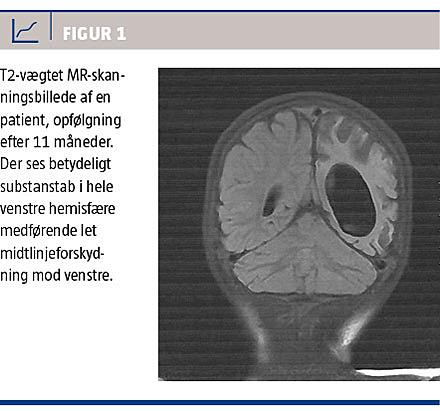

Disse neuropatologiske fund stemmer overens med de radiologiske forandringer, der ses ved HHE-syndromet, og den karakteristiske progression over tid [10] gør det muligt at differentiere tilstanden fra andre cerebrale påvirkninger. Blandt andet kan læsionerne ikke forbindes med et bestemt forsyningsområde, hvilket udelukker vaskulære læsioner, der ellers er den typiske årsag til hemiplegi. I den akutte fase ses der nogle gange tegn på cerebralt ødem på CT [7, 10], men den bedste måde at påvise de akutte forandringer er ved DW MR-skanning, hvor ophobning af vand vil vise sig som hyperintense områder. Disse områder er i de tidlige stadier primært lokaliseret til den subkortikale hvide substans, men vil i løbet af en måneds tid være erstattet af progredierende unilateral cerebral atrofi (Figur 1) [11, 12].